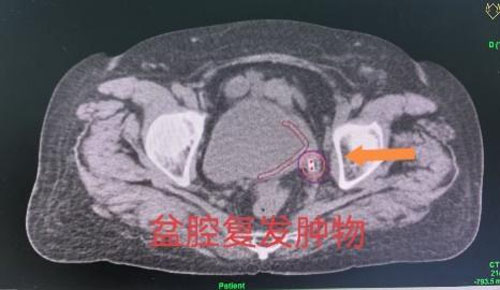

刘红教授和妇产超声科王翠菊教授团队为来访专家展示了两例疑难病例插植放疗操作的全过程。一名患者为宫颈癌IIIC1R期盆腔闭孔区域淋巴结转移。淋巴结转移是宫颈癌最常见的转移路径,同时也是影响宫颈癌患者预后最主要的危险因素之一,转移淋巴结通常需要更高的放疗剂量才能获得更好的局部控制效果。通过该项技术,在后装治疗过程中可以同时实现宫颈肿物和转移淋巴结的同步推量照射,在保护危及器官的同时,给予转移淋巴结更高的放射剂量,从而获得更好的肿瘤局部控制效果。另一名患者为宫颈癌术后膀胱后壁肿物复发。肿物体积越小,治疗效果越好,放疗的副损伤越小,但是,体积越小的肿物越难做到精准插植治疗。经腔内超声实时引导的插植技术,可以实现对微小肿物的精准定位,在确保不损伤膀胱的前提下,精准实现盆腔复发肿物的近距离放疗。